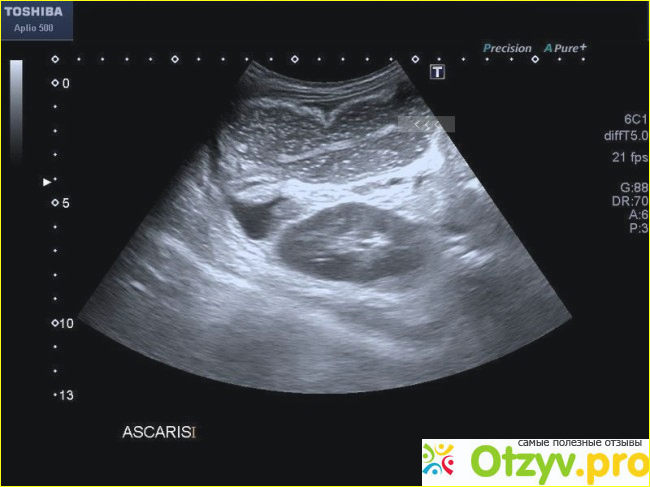

УЗИ желудочно-кишечного тракта

Ультразвуковое обследование желудочно-кишечного тракта назначается, чтобы понять как расположен желудок и кишечник, его особенности, отследить его функционирование и анатомические особенности. Также данный тип исследования проводят и с целью профилактики, чтобы проследить как протекают уже имеющиеся заболевания, имеется ли тенденция к улучшению состояния или наоборот, к запущенности процесса. Его назначают при непроходимости кишечника, подозрениях на гастриты и язвенную болезнь, возможном наличии опухолей, травматических повреждениях брюшной полости.

Проводить данное обследование нужно именно натощак. Нельзя даже пить обычной воды. Ни в коем случае нельзя курить. Только в крайнем случае, если голод крайне противопоказан, то можно немного выпить чая без сахара с сухариком. Последний прием пищи должен быть примерно в 8 вечера, при этом поесть следует очень сытно, но и легко. Ультразвуковое обследование делается обычно трансабдоминально и с помощи контрастных веществ. В последнем случае контрастирующий препарат разводится при помощи газированной воды и ее пациент должен принять перед проведением обследования. Метод имеет большое преимущество, поскольку в этом случае отсутствует лучевая нагрузка на организм. При проведении обследовании яможно и не использовать контрастирующее вещество. Таким обследованием является с применением водно-сифонной пробы. Чтобы провести данное обследование, следует выпить один литр сока или простой воды. В то время как выпитая жидкость перемещается по 12-типерстной кишке врач может оценить моторные способности органа исходя из скорости перемещения. Нередко применяется также и методика, которая в себе объединяет два метода – фиброгастроскопическое исследование и ультразвуковой метод. Этот метод называется эндосонографией. Этот вид обследования является достаточно информативным, при этом оценивается состояние желудка и стенки пищевода, а также имеется возможность обнаружения разных новообразований, которые локализуются в стенках органа.